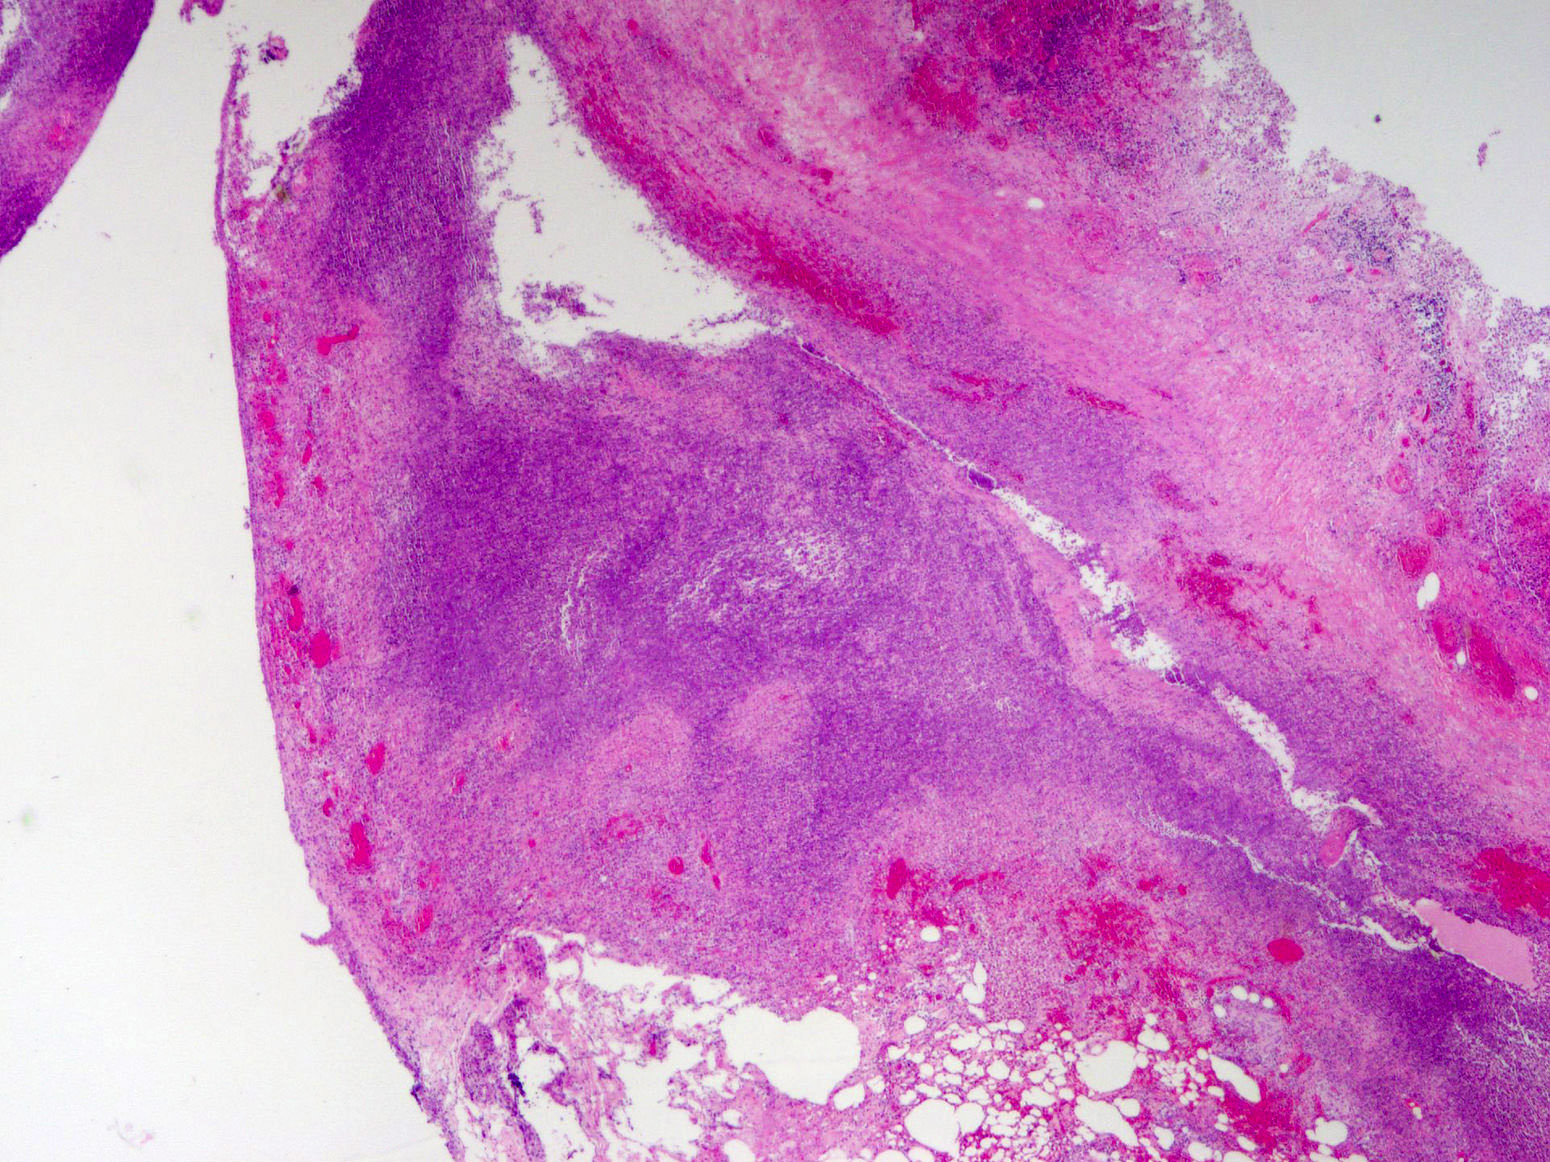

Gross description

- Gross and microscopic extent of inflammation may not correlate

- Inflammation may involve entire appendix or only a segment

- Appendix may appear grossly normal when inflammation is limited to the mucosa and submucosa

- Appendix appears swollen and erythematous when inflammation extends into the muscularis propria

- When the serosa is affected, a purulent exudate appears

- Cut surface may show hyperemia or intraluminal or intramural abscess

- Appendiceal wall may be completely necrotic in gangrenous appendicitis (J Pediatr Surg 2019;54:718)

- Perforation in severe cases

Microscopic (histologic) description

- Variable acute inflammation with predominance of neutrophils; involves some or all layers of the appendiceal wall

- Process may be divided into acute focal, acute suppurative, gangrenous and perforative

- Early lesions display mucosal erosions and scattered crypt abscesses

- Later, the inflammation extends into the lamina propria and collections of neutrophils are also seen in the lumen

- Mural necrosis in gangrenous appendicitis

- Process may be divided into acute focal, acute suppurative, gangrenous and perforative

Microscopic (histologic) images

A 40 year old caucasian man presented into the emergency room with right lower quadrant pain associated with vomiting, abdominal tenderness, fever and moderate leukocytosis. Acute appendicitis was suspected and he underwent an appendectomy. His appendix was sent to pathology for histological evaluation. The H&E images are shown above. Which of the following is the most likely diagnosis?